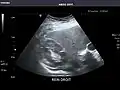

Right kidney